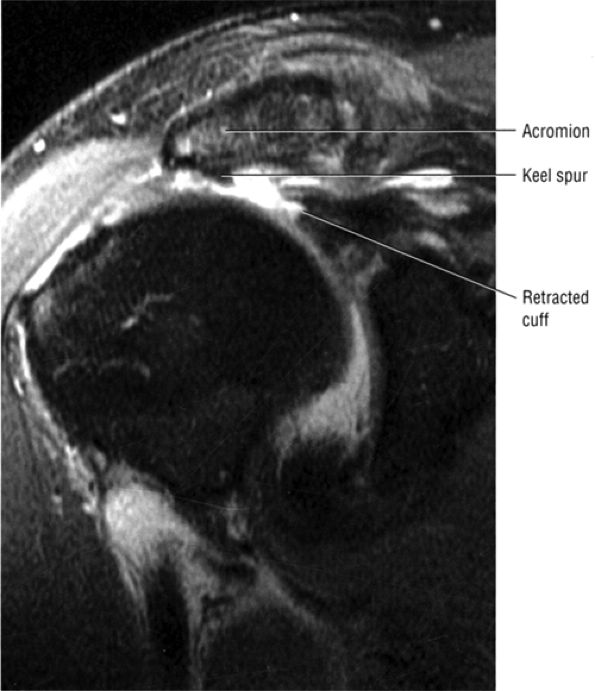

and broad-based undersurface spurs that extend along the majority of the acromial undersurface area. Inferior spurring of the distal clavicle from AC joint arthrosis can also narrow the outlet and impress upon the superior surface of the supraspinatus, leading to rotator cuff impingement and pain. Fluid and bursitis in the subacromial/subdeltoid space, often the result of impingement, are also characterized on sagittal images.

inferior surfaces of the acromion. The coracoacromial arch stabilizes the humeral head and prevents superior ascent (Fig. 8.102). The subacromial bursa is located between the acromion, the coracoacromial ligament, and the rotator cuff.44 The bursa runs from the AC joint medially, under the anterior third of the acromion and coracoacromial ligament, to a line that extends approximately 4 cm anterior and lateral to the anterolateral margins of the acromion. Anterior acromial spurs, caused by chronic irritation from the humerus in contact with this ligamentous structure, may form within the acromial portion of the coracoacromial ligament.46 Frequently, anterior acromial spurs are identified adjacent to the acromial attachment of the coracoacromial ligament. The normal low-signal-intensity acromial attachment of the coracoacromial ligament is frequently mistaken for an anterior acromial spur on coronal oblique MR images. The additive thickness of the coracoacromial ligament and the inferior acromial cortex produces this pseudospur (Fig. 8.103). In acromioplasty performed for chronic impingement, the coracoacromial ligament and the anterior inferior margin of the acromion are resected.